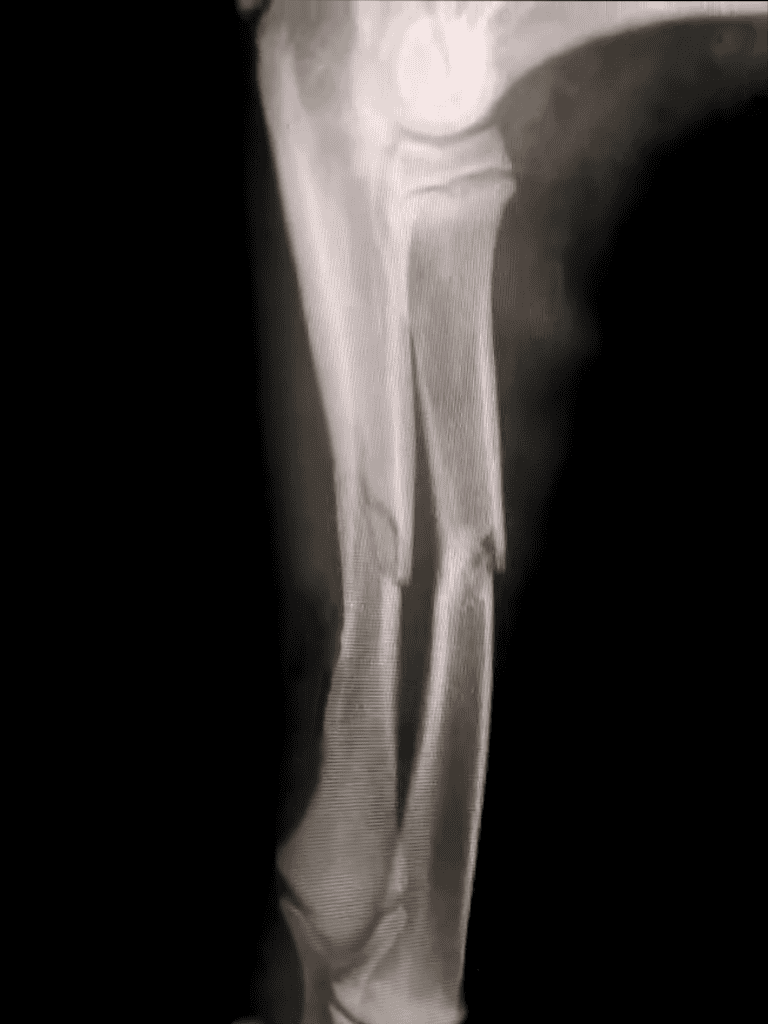

Sejo’s Injury

The car ride to the vet with Sejo was tense.

His broken leg weighed on our minds as they hoped for good news. Painkillers kept him calm, but uncertainty tugged at our hearts.

The surgery was set for Monday, two days away. Until then, Sejo relied on painkillers for relief.

The vet confirmed Sejo’s broken leg wouldn’t need surgery.

A splint and care would suffice for recovery. His bright eyes assured us he’d heal soon. Nana’s pie helped him recover.